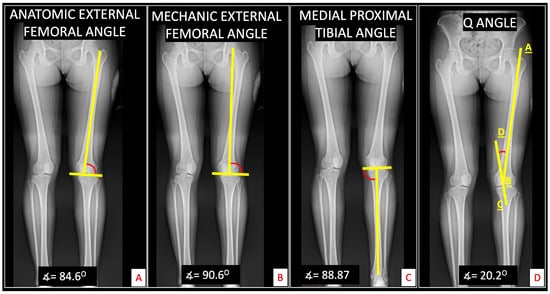

| Radiographic Variable | Group | p-Value * | |

|---|---|---|---|

| PFP | Control | ||

| Merchant angle 30° degrees | 9.0 ± 5.9 | 7.1 ± 3.6 | 0.2650 |

| Sulcus angle 30° degrees | 136.8 ± 3.8 | 132.5 ± 5.6 | 0.0140 |

| Laurin angle 30° degrees | 12.5 ± 3.2 | 18.9 ± 19.0 | 0.1817 |

| Merchant angle 60° degrees | 6.3 ± 4.3 | 5.4 ± 2.1 | 0.4204 |

| Sulcus angle 60° degrees | 137.2 ± 5.2 | 135.4 ± 4.6 | 0.2897 |

| Laurin angle 60° degrees | 15.7 ± 6.1 | 16.7 ± 4.6 | 0.5852 |

| Merchant angle 90° degrees | 4.9 ± 1.6 | 5.7 ± 1.7 | 0.1657 |

| Sulcus angle 90° degrees | 140.8 ± 4.5 | 139.0 ± 4.2 | 0.2395 |

| Laurin angle 90° degrees | 15.7 ± 3.3 | 17.8 ± 3.6 | 0.0893 |

| Tibio–calcaneal angle | 15.5 ± 4.8 | 13.2 ± 5.5 | 0.1978 |

| Mechanic external femoral angle | 88.8 ± 3.2 | 90.4 ± 2.5 | 0.1044 |

| Anatomic external femoral angle | 84.0 ± 4.0 | 82.9 ± 1.9 | 0.3130 |

| Medial proximal tibial angle | 88.2 ± 2.0 | 88.6 ± 2.5 | 0.6058 |

| Q angle | 12.8 ± 9.1 | 11.9 ± 6.4 | 0.7463 |